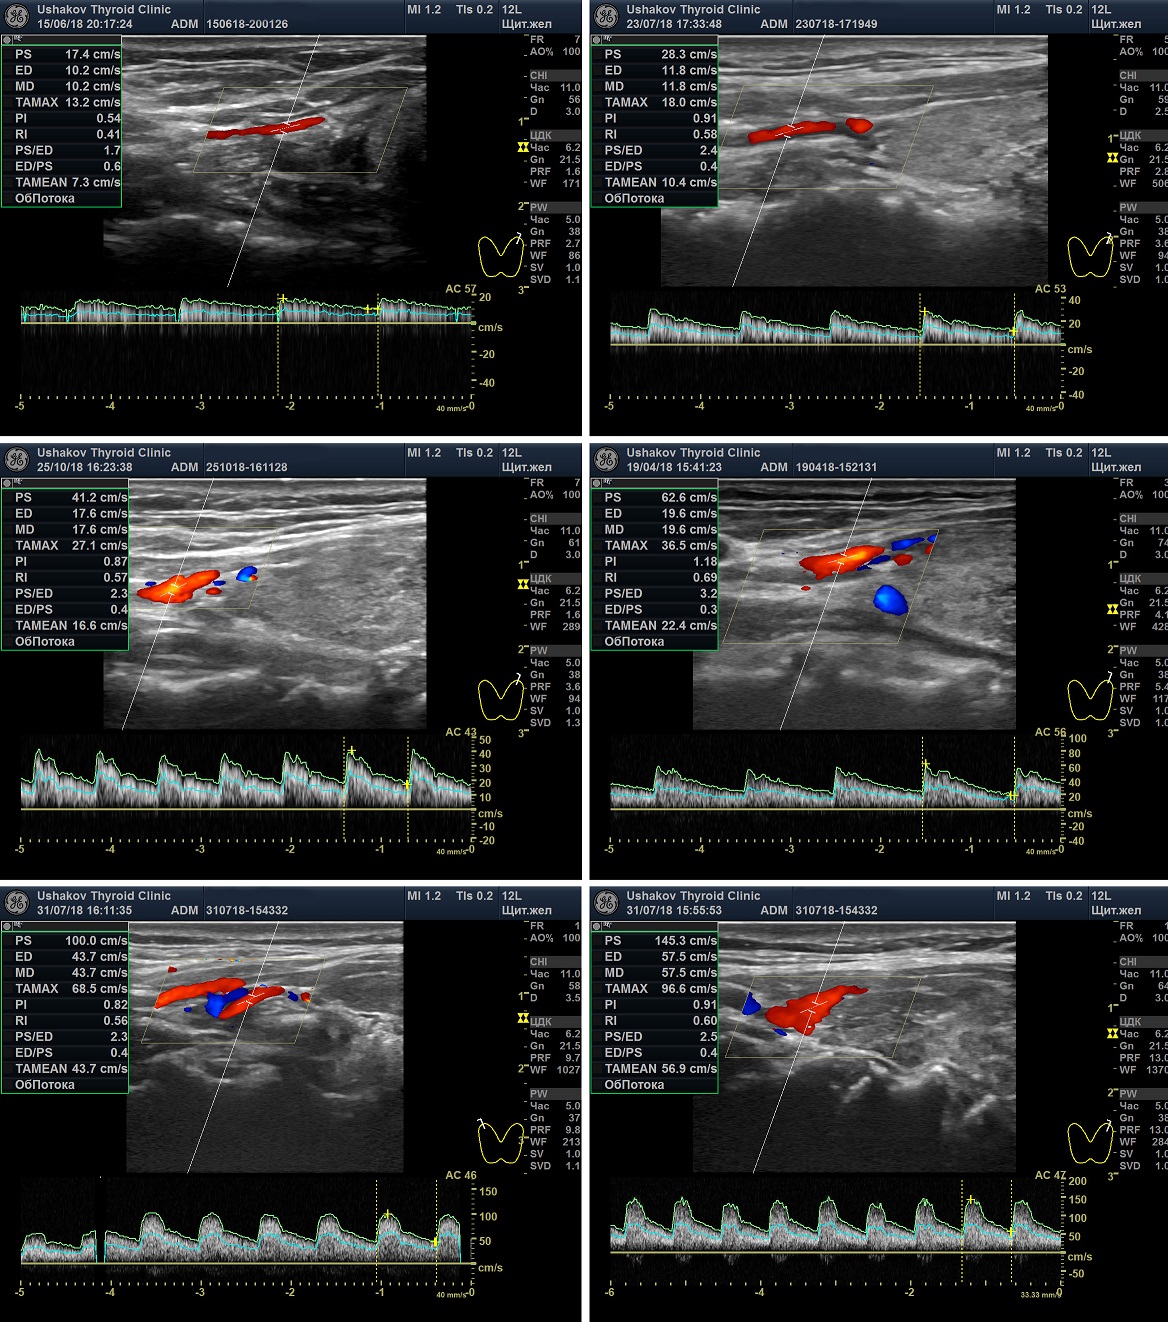

Варианты оценки Пиковой Систолической Скорости Кровотока

(По данным Клиники щитовидной железы доктора А.В. Ушакова, 2018)

Ослабленная ПССК ― менее 20 см/с.

Нормальная ПССК ― 20-30 см/с.

Оптимальная ПССК ― 23-28 см/с.

Малое усиление ПССК ― 30-50 см/с.

Умеренное усиление ПССК ― 50-80 см/с.

Значительное усиление ПССК ― более 80 см/с,

Очень значительное усиление ПССК ― более 120 см/с.

Рисунок 5. Варианты Пиковой Систолической Скорости Кровотока (ПССК). Спектральная допплеровская диагностика кровотока щитовидной железы. Представлены основные случаи ПССК: Ослабленная, Нормальная, Малого усиления, Умеренного усиления, Значительного и Очень значительного усиления.

Если имеется усиление ПССК, то приходится судить об усиленном влиянии на ткань щитовидной железы и её сосуды со стороны периферической вегетативной нервной системы (пВНС). Увеличение ПССК может определяться при разных состояниях гормонального обмена ― эутиреозе, гипотиреозе и гипертиреозе. Это связано с ведущей ролью пВНС в деятельности щитовидной железы.